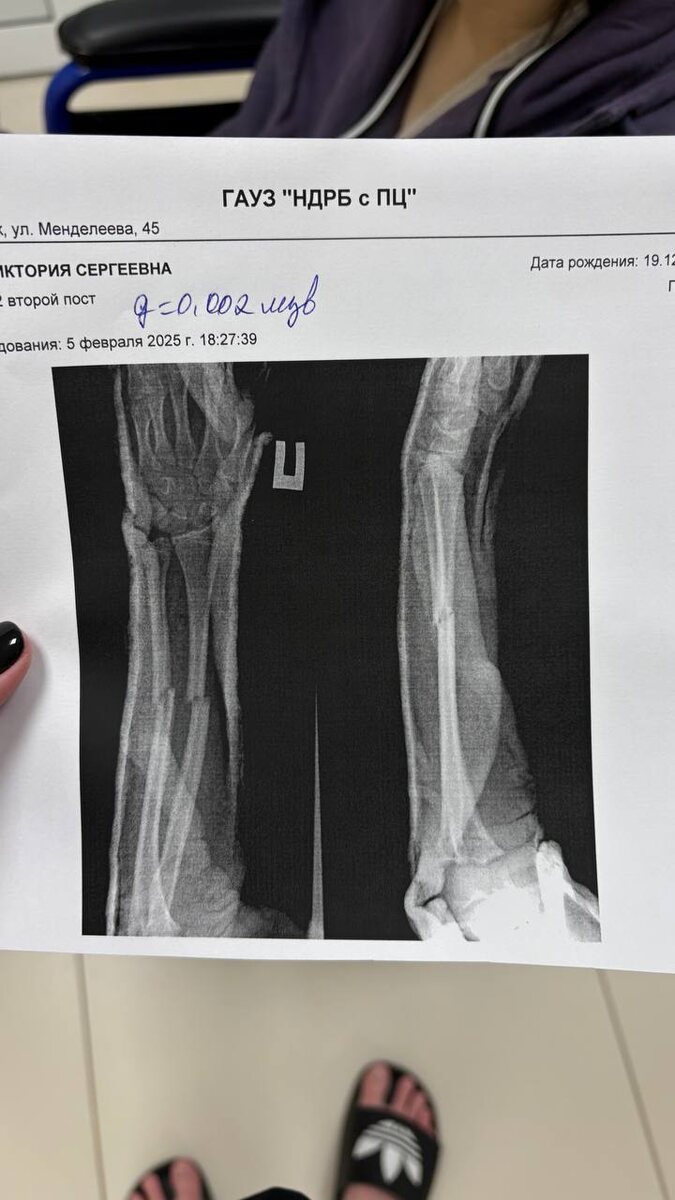

5 февраля 2025 года в школе № 6 г. Нижнекамска абу-бандит из 6-го класса подошёл к русской девочке и спросил: «Тебя когда-нибудь бросали через прогиб?». Девочка естественно посмотрела на него как на больного идиота и постаралась уйти, но он схватил её за руку и бросил со всей силы об пол. В результате девочка получила закрытый перелом обеих рук и была экстренно госпитализирована. Её прооперировали и теперь ей потребуется длительная реабилитация.